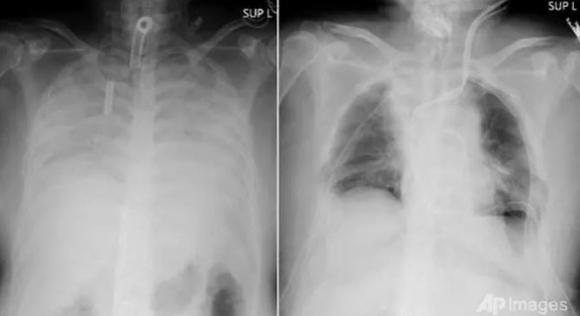

Phim X-quang chụp phần ngực bệnh nhân trước khi phẫu thuật (bên trái) và sau khi phẫu thuật (ảnh do Bệnh viện Đại học Kyoto cung cấp ngày 9-4) - Ảnh: AP/channelnewsasia.com

Theo báo Asahi (Nhật), người được ghép phổi là một nữ bệnh nhân sống tại vùng Kansai. Chị bị mắc COVID-19 từ cuối năm ngoái, sau ba tháng điều trị, căn bệnh đã gây các triệu chứng viêm phổi nghiêm trọng tới mức phải nằm máy thở.

Tuy nhiên ngay cả khi cơ thể người bệnh không còn virus corona, phổi vẫn tiếp tục co lại và xơ cứng dần. Do đó bệnh viện quyết định phẫu thuật ghép phổi cho chị, với phần tạng hiến từ hai người còn sống là chồng và con trai của bệnh nhân theo nguyện vọng của gia đình.